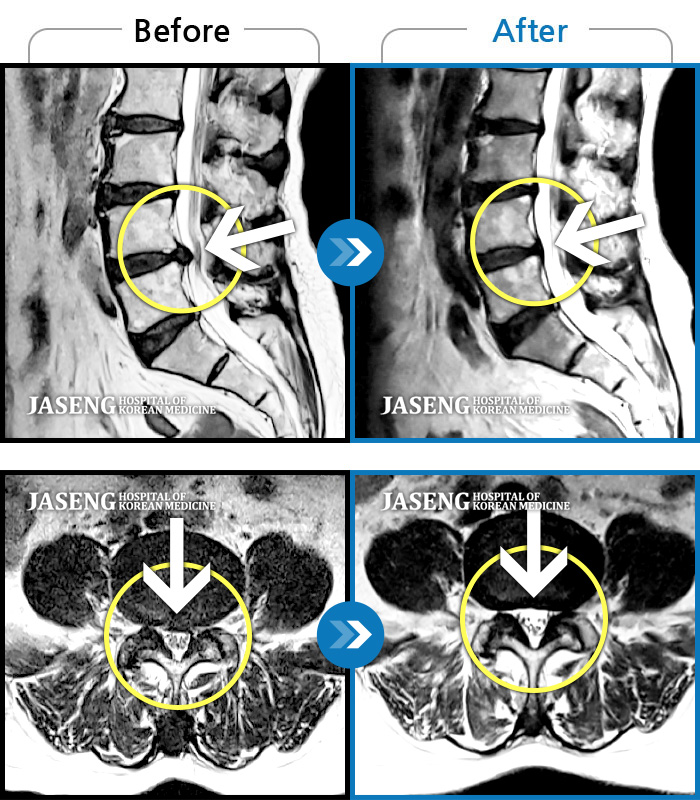

Before

After

환자에게 사전 동의를 받아 동일 조건에서 촬영되었습니다.

개인에 따라 치료 후 부작용이 발생할 수 있으니 의료진과 상담 후 치료를 진행하시기 바랍니다.

양측 허리부터 좌측 다리까지 이어지는 저림과 통증으로 걷기 힘들어 내원하였습니다.

기침하다가 주저앉았어요. 지금은 양측 다리가 당겨요.